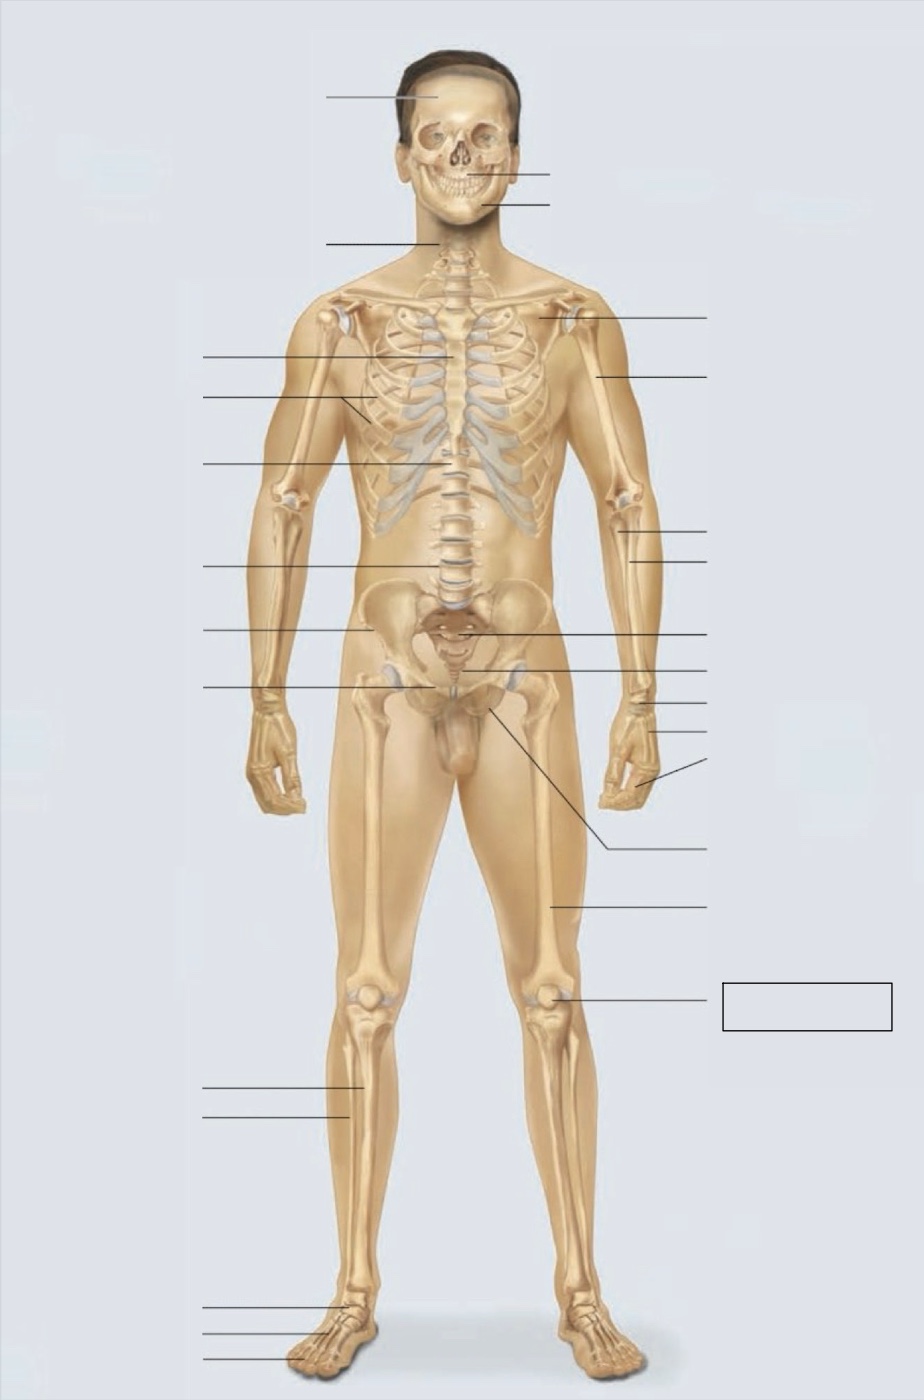

maxilla

mandible

scapula

humerus

ulna

radius

sacrum

coccyx

carpals

metacarpals

phalanges

ischium

femur

patella

phalanges

metatarsals

tarsals

fibula

tibia

pubis

ilium

lumbar vertebrae (L4)

thoracic vertebrae (T11)

ribs

sternum

cervical vertebrae

skull